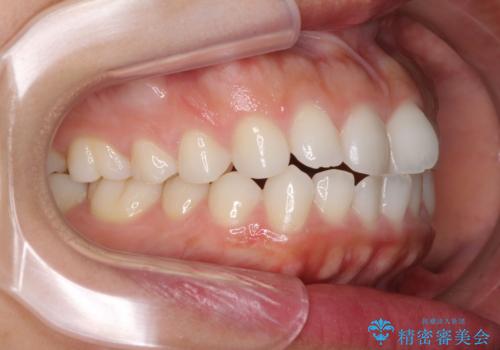

- 口元の突出感を気にして来院された患者様です。

上下左右の第一小臼歯4本を抜歯して口元を下げる治療計画としました。